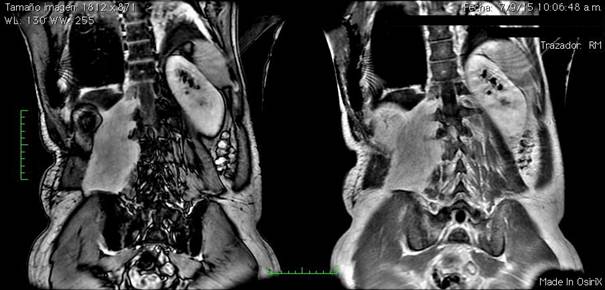

Hasta este punto nos encontrábamos frente a una probable neoplasia intra-torácica de estirpe epitelial. Restaba descifrar el origen de la misma, así como el de la tumoración paravertebral. Para esto, se realizó una resonancia magnética (RM) tórax-abdomen que confirmó los hallazgos imagenológicos aportados por la tomografía: proceso expansivo de 146 mm L x 82 mm T x 78 mm AP, con señal similar a músculo, que invade psoas y músculo ilíaco derechos, insinuándose por agujeros intervertebrales de L4, L3, L2 y L1 sin invadir el conducto raquídeo. Contacta el pilar diafragmático derecho. Pleura basal derecha engrosada con un patrón nodular sin clara evidencia de invasión directa. Lesiones tumorales a nivel de músculos intercostales derechos en contigüidad con proceso pleural descrito. No se observan nódulos pulmonares ni adenomegalias mediastinales. Hígado sin lesiones. No se identifica glándula suprarrenal derecha la cual puede estar englobada por la tumoración descrita. Conglomerado de adenomegalias rodeando al tronco celíaco y múltiples adenomegalias a nivel latero-aórtico izquierdo (Figuras 3 y Figura 4).

Figura 3: Resonancia abdomen: Proceso expansivo de 146 mm L x 82 mm T x 78 mm AP, con señal similar a músculo, que invade psoas y músculo ilíaco derechos, insinuándose por agujeros intervertebrales de L4, L3, L2 y L1.